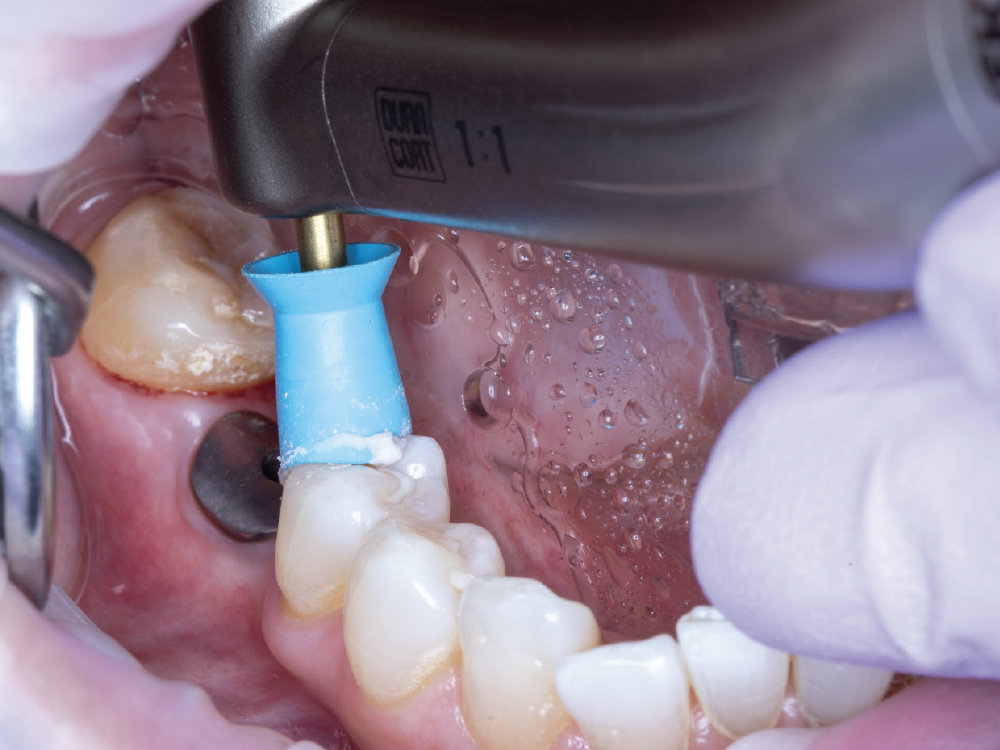

Capture the Surrounding Soft Tissue Immediately

Capture the Surrounding Soft Tissue Immediately. Scan the peri-implant soft-tissue architecture as soon as the scan body is placed, before the tissue collapse occurs. Gingival tissues begin to collapse and distort within minutes of scan body insertion, and the initial tissue contours are critical for creating proper emergence profiles. Work efficiently but thoroughly to document the tissue topography in its most accurate state.